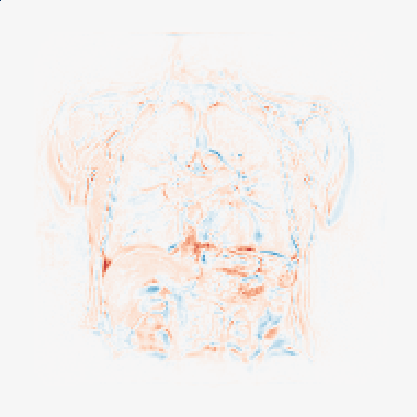

Finally, in Figure 2, we present the deformed image produced by the proposed method on coronal view for a single patient in the two different moments of the respiratory cyrcle. The grids were superimposed on the images, indicating the displacements calculated by the network. The last column shows the difference between the reference and deformed image. One can observe that the majority of the errors occur on the boundaries, as the network fails to capture large local displacements.

To asses the relevance of the decoded transformations in a clinical setting, we trained a small classifier on top of the obtained residual deformations to classify patients as healthy or unhealthy. The residual deformation associated with a pair of images indicates voxel displacements, written as , where is the deduced deformation between the two images, and is the identity deformation.